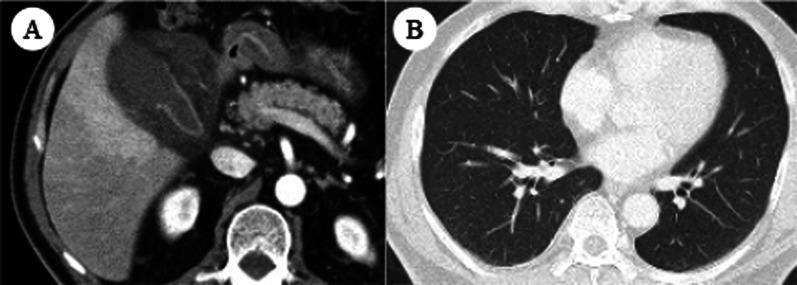

A 56-year-old man presented to our hospital with abdominal pain. Computed tomography revealed intraluminal membranes, an irregular or absent wall, and an abscess of the gallbladder, indicating acute gangrenous cholecystitis. Early laparoscopic cholecystectomy seemed to be indicated; however, a COVID-19 antigen test was positive despite no obvious pneumonia on chest computed tomography and no symptoms. After discussion among the multidisciplinary team, antibiotic therapy was started and percutaneous transhepatic gallbladder drainage (PTGBD) was planned for the following day because the patient's vital signs were stable and his abdominal pain was localized. Fortunately, the antibiotic therapy was very effective, and PTGBD was not needed. The cholecystitis improved and the patient was discharged from the hospital on day 10. One month later, laparoscopic delayed cholecystectomy was performed after confirming a negative COVID-19 polymerase chain reaction test result. The postoperative course was uneventful, and the patient was discharged on postoperative day 2 in satisfactory condition.

一名56岁男性因腹痛前来我院就诊。计算机断层扫描显示胆囊腔内有隔膜、胆囊壁不规则或消失以及脓肿,提示急性坏疽性胆囊炎。似乎应尽早进行腹腔镜胆囊切除术;然而,尽管胸部计算机断层扫描未显示明显肺炎且无相关症状,但COVID-19抗原检测呈阳性。多学科团队讨论后,由于患者生命体征稳定且腹痛局限,开始给予抗生素治疗,并计划次日进行经皮经肝胆囊引流术(PTGBD)。幸运的是,抗生素治疗非常有效,无需进行PTGBD。胆囊炎有所改善,患者于第10天出院。1个月后,在确认COVID-19聚合酶链反应检测结果为阴性后,进行了腹腔镜延迟胆囊切除术。术后过程顺利,患者于术后第2天状况良好出院。